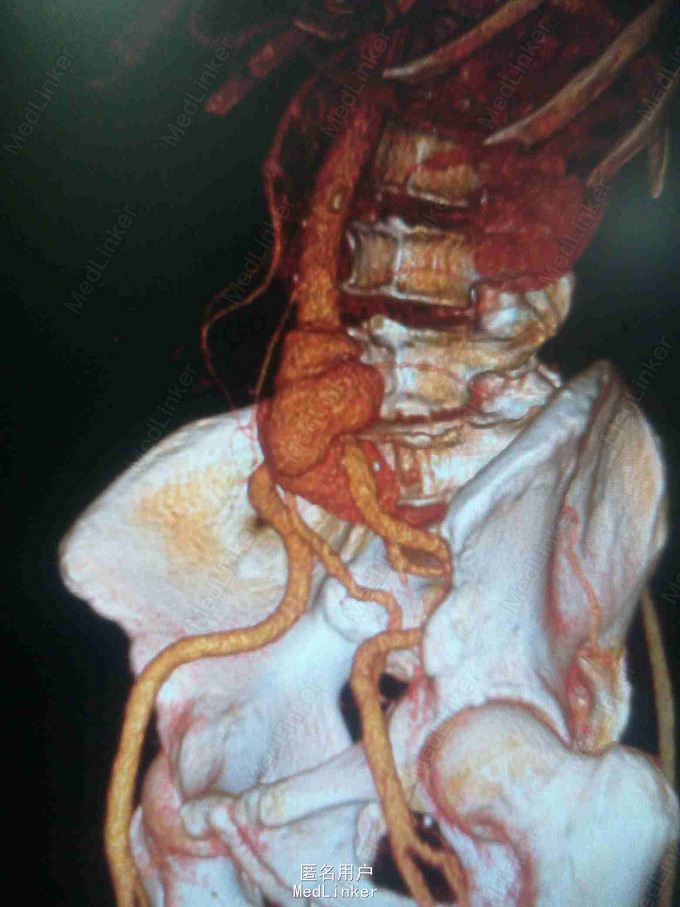

体查:下腹部可触及搏动性包块。 辅助检查:腹部CT:腹主动脉假性动脉瘤并血栓形成,腰5椎体受侵蚀。血培养:沙门氏菌。

诊断:沙门氏菌感染性腹主动脉假性动脉瘤 处理:急诊行腹主动脉瘤切除人工血管置换术,术后予美罗培南抗感染8周,续以左氧氟沙星口服。

讨论:感染性腹主动脉假性动脉瘤较少见,致病菌以沙门氏菌最为常见。常见的手术方式为原位重建,旁路重建及支架植入,其中支架植入尚存较大争议。术后感染复发及死亡率仍较高,均需长时间抗感染治疗。